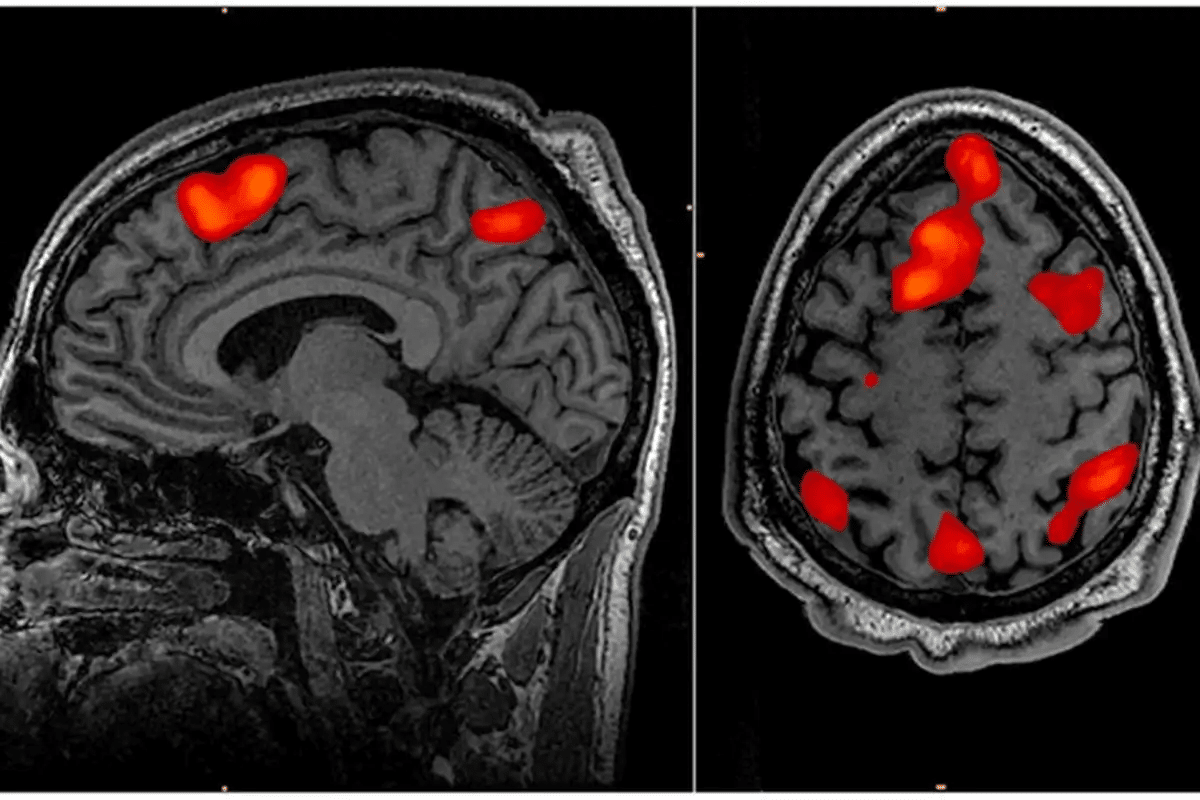

Neuroimaging is a big part of diagnosing brain vasculitis. MRI (Magnetic Resonance Imaging) and angiography show blood vessel problems. Blood tests and lumbar punctures help rule out other conditions.

Brain vasculitis can cause cognitive dysfunction, leading to mental changes and impairments. This symptom greatly affects patients’ lives. We will look at how brain vasculitis impacts memory, mood, and personality. We will also discuss how doctors assess cognitive function in these cases.

Memory and concentration issues are common in brain vasculitis. Patients might struggle to remember things or stay focused. These problems can start small but worsen over time. Early detection is key to slow down cognitive decline.

Vasculitis inflammation can harm brain areas that handle memory and focus. This makes daily tasks harder. It’s important to see these symptoms as signs of brain health issues.

When brain vasculitis is suspected, a detailed cognitive assessment is done. This checks memory, attention, language, and problem-solving skills.

We use specific neuropsychological tests to measure cognitive function. These tests show how severe the impairment is and if it’s getting worse. The results help us decide on the best treatment for each patient.